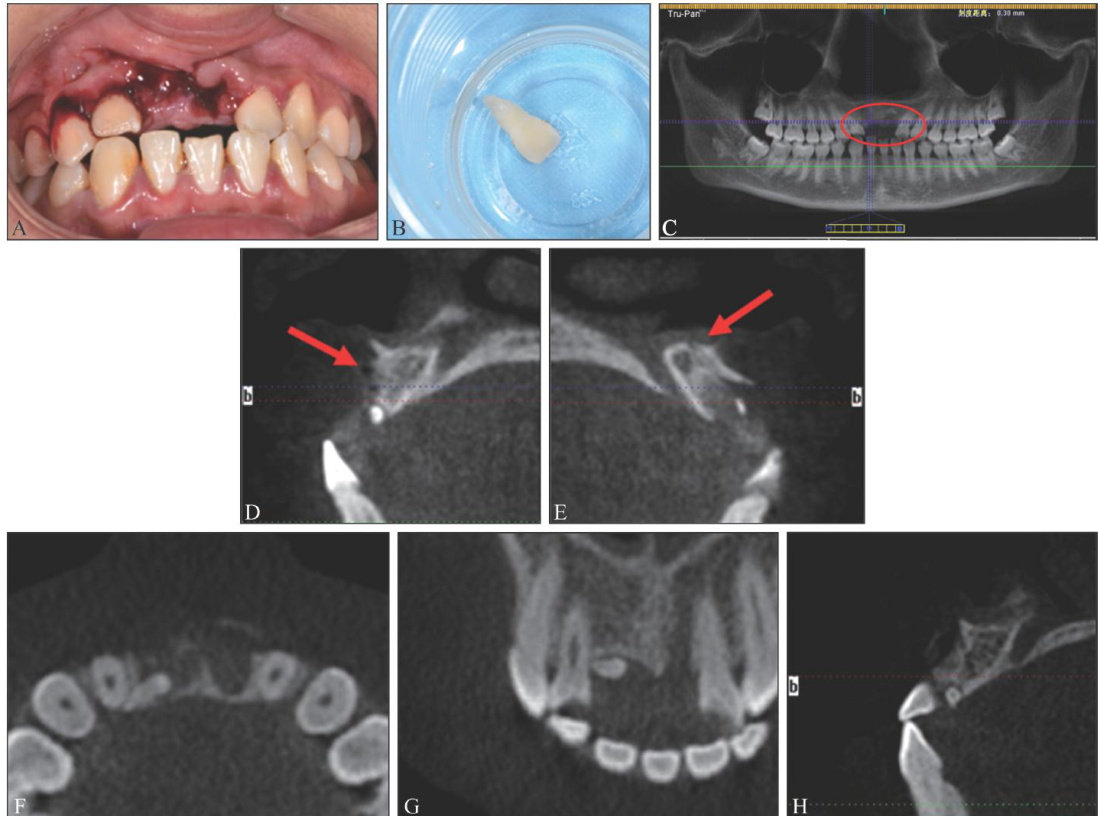

[摘要]牙外伤是口腔临床工作中较为常见的急症之一,发病率高,上颌中切牙最易受累。本文报告1例17岁女性患者,因外伤导致11、21牙完全脱位,21牙脱位后遗失,11牙因唇侧牙槽骨壁缺如导致再植术预后差,因此将11牙体外根管治疗后再植于条件较好的21牙牙槽窝内,并行弹性夹板固定。(剩余9348字)

上颌中切牙完全脱位后异位牙再植及延期种植修复1例